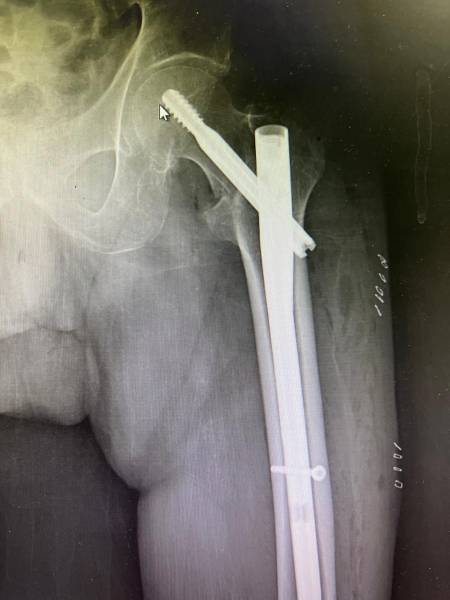

- إجراء عمليات جراحية معقدة و دقيقة في مجال العظام و المفاصل و الكسور و الإصابات ، رغم الضغط الكبير على المستشفى و أعداد المراجعين الكبيرة.

- تطبيق تقنيات جراحية حديثة و متقدمة، و ذلك في ظل التحديات التي يواجهها الفريق بسبب أعداد المرضى و المراجعين الكبيرة.